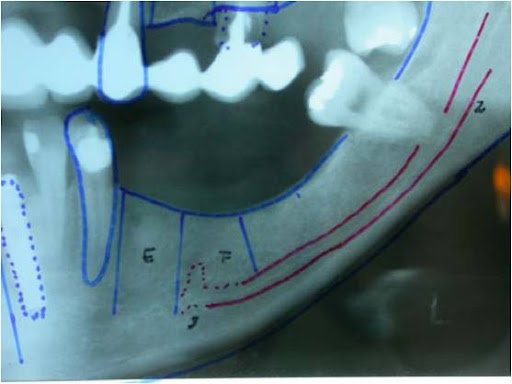

Radiograficamente, além do planejamento para os implantes, são avaliados todo o trajeto do nervo alveolar e a posição do forame mentoniano, utilizando-se da ortopantomografia, ou ainda de tomografia computadorizada (16).

Pode-se com isso fazer um traçado predicativo do local das osteotomias e, na tomografia, avaliar densidade do osso medular, a espessura das corticais e, as medidas precisas da posição do canal mandibular em todo seu trajeto

Fig. 1 - Radiografia ortopantomográfica mostrando o traçado do canal do nervo alveolar inferior.